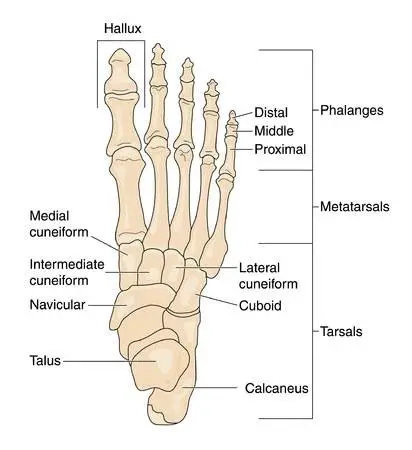

Then you may have cuboid syndrome. The cuboid is one of 26 bones in your foot. The bones, along with the ligaments and muscles, need to hold up your body weight when you stand and absorb the shock from walking, running, and jumping.

Your cuboid is pretty stable when you consider all the ligament attachments. A muscle tendon called the peroneus longus also forms a sling around the side of the cuboid. The cuboid becomes the pulley for the peroneus longus, pulling it up and over towards the middle – a movement called eversion.

Clinicians might look for a slight depression around the cuboid on the top of the foot, or a protrusion on the bottom. These changes can be subtle. Additional indicators may include tenderness of the peroneus longus tendon or at the origin of the extensor digitorum brevis muscle. Direct pressure on the cuboid from the top of the foot, when combined with other observations, can also be suggestive of cuboid syndrome.